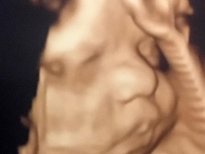

Anne adayları için en heyecanlı an olan bebeğin anne karnında ilk görüntüleri, görenlere 'Adeta poz vermiş' dedirtiyor. 16'ncı haftadan itibaren yüzü şekillenmeye ve gelişmeye başlayan bebeklerin ultrasonla çekilen fotoğrafları arasında kaşları çatık, gülen, eliyle yüzünü kapatan, burnuyla oynayan, parmağını emen, elini çenesine dayayan bebekler olduğu gibi kendini göstermeyen bebekler de var.